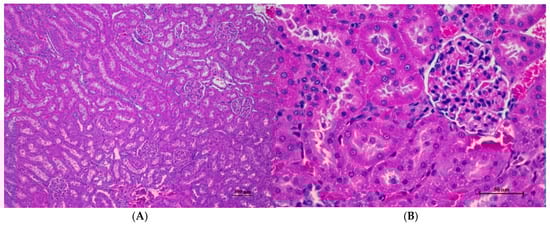

Figure 7.

Histopathological examination of rat kidney tissue in sub-acute toxicity from daily (28 days) fed oral dose of CDF revealed normal histological structure. (A) The renal tissue exhibited intact glomeruli and well-organized renal tubules (100×, H&E). (B) High magnification showed normal size and cellular composition of glomeruli. The surrounding renal tubules demonstrated well epithelial lining with intact cellular morphology (400×, H&E).

Histopathological analysis of rat organs following 28-day cassava fiber administration revealed mild hepatocellular swelling and vacuolation in the liver, deemed within normal limits, while the kidneys, heart, and spleen exhibited no significant lesions; however, the lungs consistently displayed moderate to severe alveolar edema, septal engorgement, hemorrhage, and inflammatory cell infiltration, suggesting a potential pulmonary response to the cassava fiber, despite the absence of overt clinical toxicity.